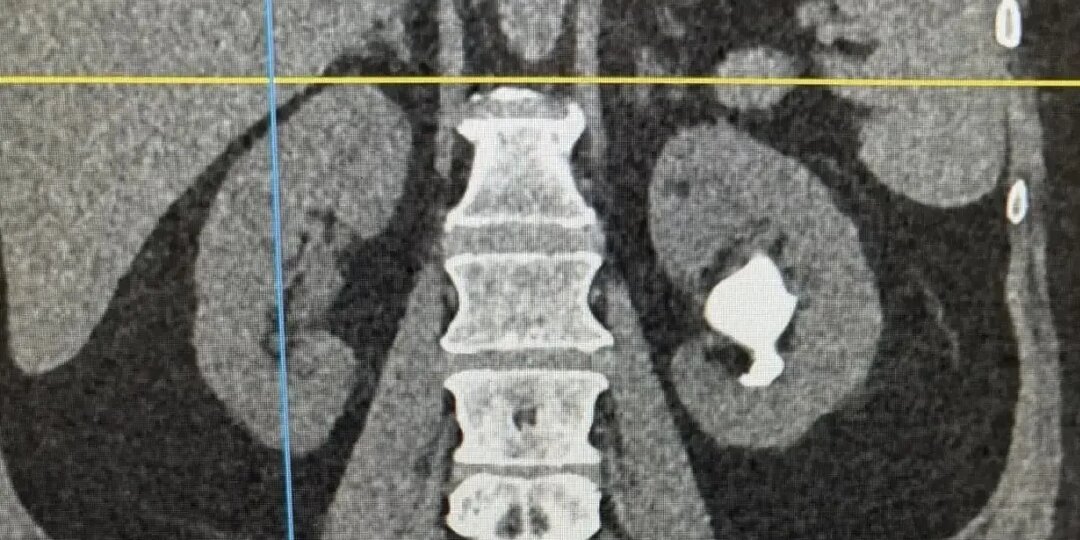

Врачи удалили крупный камень и сохранили почку женщине в Кемерове

Урологи больницы имени Подгорбунского провели сложную операцию пациентке с большим коралловидным камнем в почке. Раньше в таких случаях орган часто удаляли, но сейчас его удалось сохранить. Лечение прошло в два этапа: сначала сняли воспаление и восстановили отток мочи, затем через небольшой прокол раздробили и удалили камень. Самый крупный фрагмент достигал 6 см. Вся операция заняла около часа.